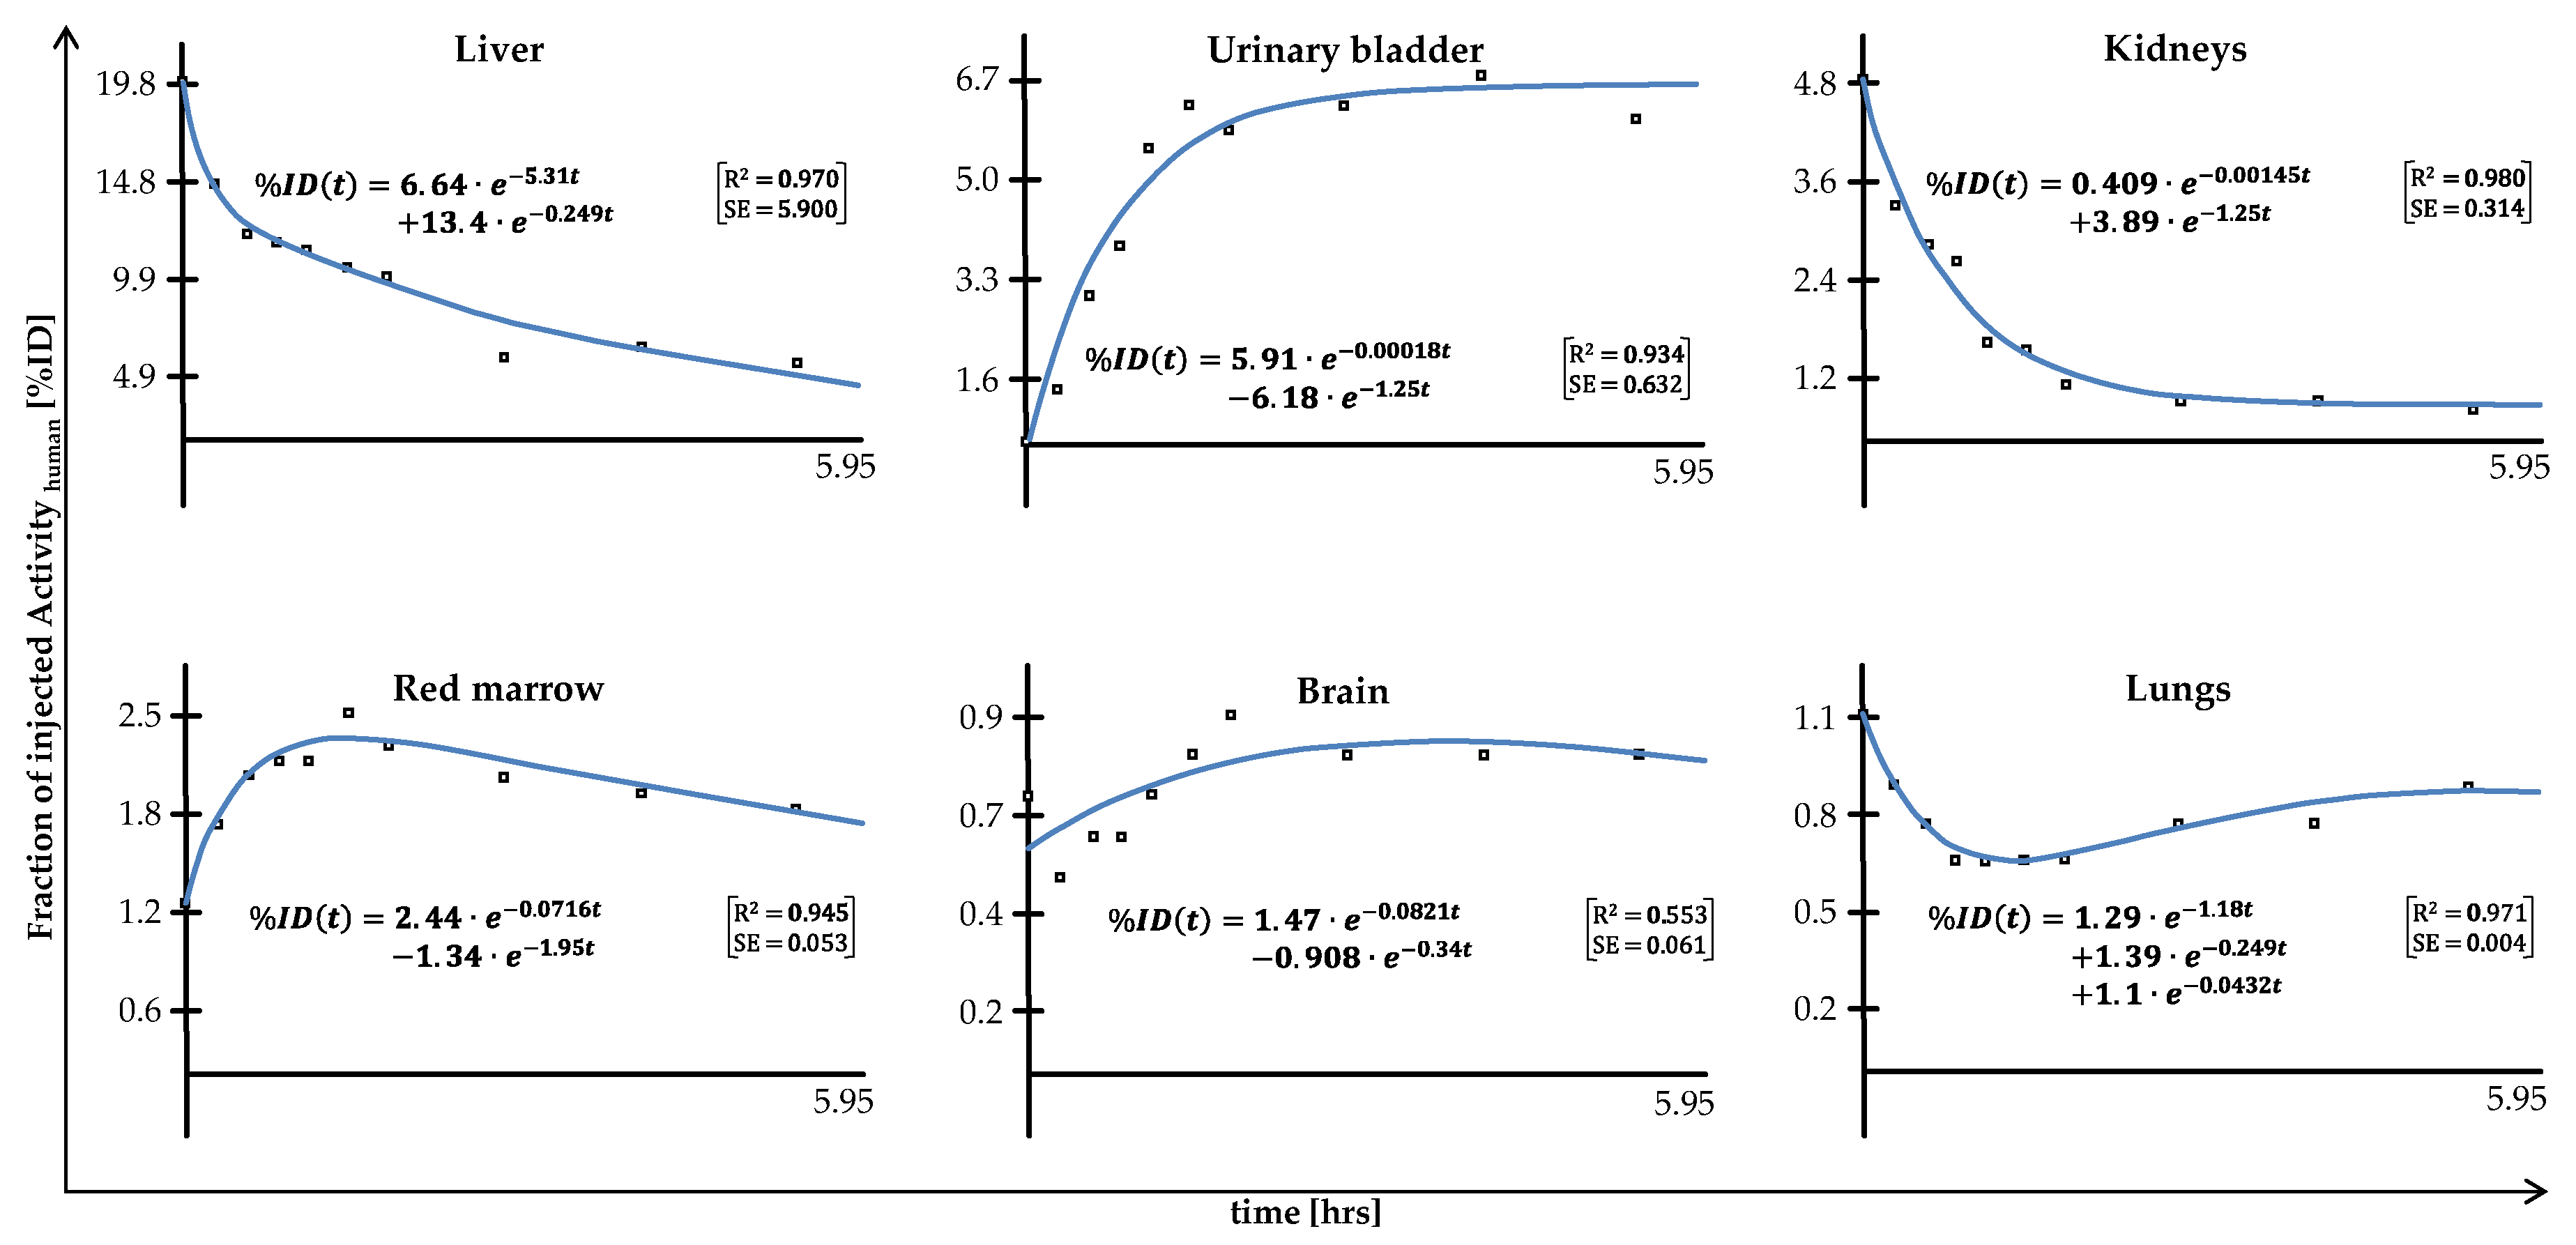

2. Results

3. Discussion

4.2. Preclinical Dosimetry Studies—In Vivo PET/CT Imaging in Pigs

4.3. Image Analysis

4.4. Incorporation Dosimetry